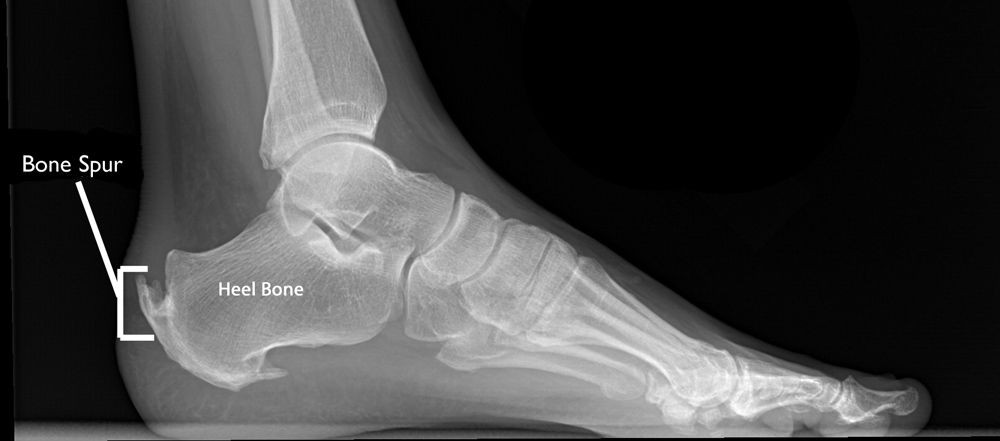

Ayakta durmayı güçleştiren, topuktaki şiddetli ağrıya sebep olan rahatsızlığa topu dikeni denir. Kalkaneal spurs olarak bilinen topuk dikeni, topuktaki kalsiyum birikmesinin bir sonucudur. Kimi zaman ayakta durmayı bile güçleştiren bu rahatsızlıktan cerrahi yöntemle kurtulmak mümkün.